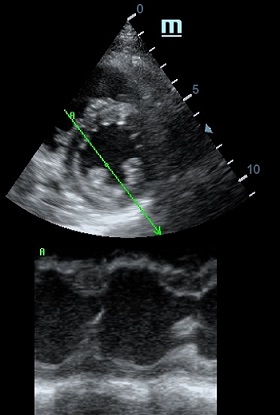

Но как же провести стандартные измерения в М-режиме, если мы его не использовали? На помощь приходит функция Free Xros M – анатомический М-режим. Имея записанную в память прибора видео петлю, мы можем провести линию М-режима в любом месте, при этом корректируя изначально не оптимальный угол.

Оценка кооптации нижней полой вены ещё никогда не была такой простой и точной, никаких лишних деталей, просто устанавливаем клипер по анэхогенному участку.